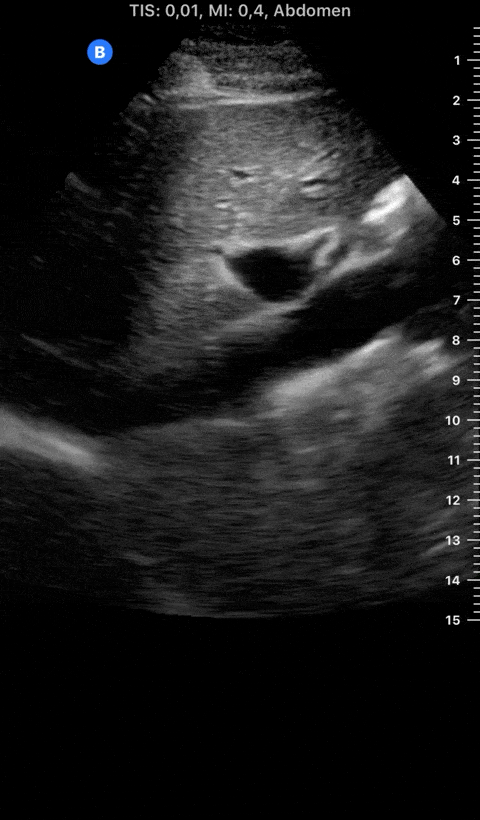

INFERIOR VENA CAVA VIEW

Coming from the subxiphoid view, scan longitudinally and slightly to the right of the body’s midline, with the orientation marker towards the head. Identify the landmarks and differentiate between the aorta and IVC by dragging the probe to the sides. Then slide the probe upwards, following the IVC as it traverses the diaphragm to enter the RA. Measure the IVC about 2 cm caudal to the RA entrance or 1 cm caudal to the hepatic vein inlet, but not at the level of the diaphragm. Measure the maximum IVC diameter, which will be in expiration, in two planes. Then measure the minimum IVC diameter using the sniff test: ask the patient to sniff quickly, causing the intrathoracic pressure to fall rapidly and a normal IVC to collapse. M-mode has been proposed to capture maximum and minimum diameters on a single image; however, this is not recommended, considering the IVC is displaced upwards with the respiratory movements (2).